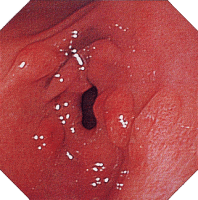

内視鏡所見

縦走潰瘍 敷石像 不整形潰瘍

クローン病画像 クローン病画像 クローン病画像

提供:牧山和也先生